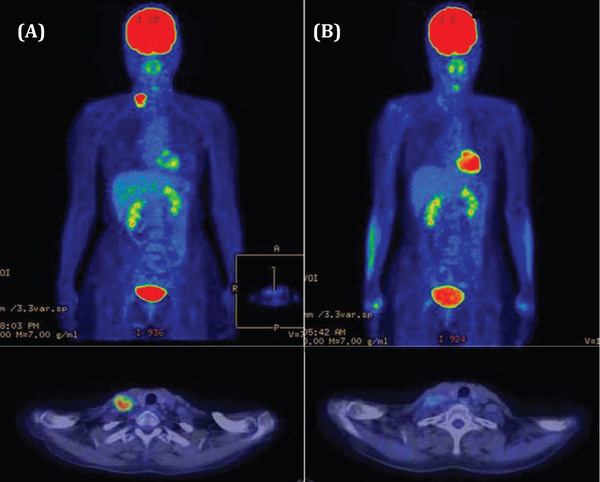

Trong khi đó, các phương pháp chẩn đoán hình ảnh khác như chụp cắt lớp vi tính, cộng hưởng từ, siêu âm chỉ phát hiện và đánh giá được các tổn thương khi đã có những thay đổi về cấu trúc giải phẫu ở mức độ đủ lớn và bỏ qua các tổn thương có đường kính dưới 1cm. Mặt khác, ở những bệnh nhân ung thư sau phẫu thuật, xạ trị, hóa trị, các tổn thương có thể biến dạng, thay đổi cấu trúc nên hình ảnh CT/ MRI vẫn có những hạn chế trong việc xác định các tổ chức còn sót tế bào ung thư, không phân biệt được các tế bào xơ hóa với tái phát và di căn. Cũng nhờ khả năng ghi nhận chính xác những bất thường PET/CT không những được dùng trong việc phát hiện sớm ung thư mà còn được dùng để đánh giá các phát triển của ung thư, sự di căn hay phát triển của ung thư tới các cơ quan khác của cơ thể hay sự tái phát của bệnh.

Tại Việt Nam, ngoài Bệnh viện Chợ Rẫy, tổ hợp máy PET/CT cũng đã được trang bị tại Bệnh viện Việt Đức, BV Bạch Mai, BV trung uong Quân đội 108. Vậy, ai nên chụp PET/CT?Khi nào bệnh nhân nên chụp PET/CT là câu hỏi thời sự? Những bệnh nhân có nguy cơ cao đối với ung thư hoặc những bệnh nhân sau khi thử gen, thử máu phát hiện một số chỉ điểm về ung thư thì nên chụp PET/CT để kiểm tra. Bệnh nhân nên chụp PET/CT khi có chỉ định của bác sĩ chuyên khoa. Những bệnh nhân không có những bệnh lý liên quan đến ung thư thì không cần chụp PET/CT. Hoặc trường hợp bệnh lý mà dựa trên kinh nghiệm và các chẩn đoán lâm sàng, thầy thuốc có thể chẩn đoán chính xác loại bệnh ung thư, các giai đoạn tiến triển của ung thư thì cũng không cần chụp PET/CT. Ví dụ ung thư tuyến giáp được chỉ định chụp PET/CT rất ít vì mức độ bệnh đến đâu có thể ước đoán chính xác. Những loại ung thư không tăng sinh hoạt động với glucose cũng được cân nhắc trước khi chụp PET/CT, phụ nữ có thai không chụp PET/CT.

PET/CT có tác dụng với tất cả ung thư? Nói chung, PET/CT có thể phát hiện được khoảng 80% các loại ung thư vì việc tăng sinh hoạt động với glucose là phổ biến ở các tế bào ung thư, song cũng có một số tế bào ung thư không tăng sinh hoạt động với glucose, chỉ tăng sinh hoạt động chuyển hóa chất khác như mỡ, đạm, thì có thể khó phát hiện. Một phương pháp được áp dụng phổ biến cho toàn thân thì lại không đặc hiệu và ngược lại. Ví dụ, nghi ngờ ung thư vú thì phương pháp chẩn đoán đầu tiên được nghĩ đến là nhũ ảnh, ung thư cổ tử cung thì phết tế bào,... Đây là những phương pháp rẻ tiền nhưng lại rất hiệu quả.

PET/CT là phương pháp tầm soát hữu hiệu nhưng không thể phổ cập toàn dân vì chi phí khá cao. Bởi vậy, quan điểm sử dụng PET/CT vẫn còn bàn luận trên thế giới. Để đưa vào chương trình quốc gia, phương tiện tầm soát phải đáp ứng yêu cầu: độ nhạy cao, gía rẻ, dễ di chuyển để phục vụ cho số đông bệnh nhân ở vùng sâu, vùng xa. Ở nước ngoài cũng chỉ chụp PET/CT cho những người có nguy cơ cao. Nhược điểm lớn nhất của PET/CT hiện nay là chi phí quá cao, vì thế không có nhiều người bệnh được tiếp cận với phương pháp tầm soát này. Hiện chỉ có một số ít bệnh nhân khá giả mới có khả năng chụp PET/CT. Hiện nay đơn vị PET/CT đang đề xuất đưa dịch vụ PET/CT vào danh sách bảo hiểm y tế để phương tiện chẩn đoán hiện đại này đến được nhiều bệnh nhân hơn.

Chụp PET/CT phát hiện được khoảng 80% các loại ung thư và hỗ trợ việc đánh giá hiệu quả của các phương pháp điều trị. Những bệnh nhân có nguy cơ cao đối với ung thư hoặc những bệnh nhân sau khi thử gen, thử máu phát hiện một số chỉ điểm về ung thư thì nên chụp PET/CT để kiểm tra. PET/CT có thể phát hiện được khoảng 80% các loại ung thư vì việc tăng sinh hoạt động với glucose là phổ biến ở các tế bào ung thư, tuy nhiên, cũng có một số tế bào ung thư không tăng sinh hoạt động với glucose, chỉ tăng sinh hoạt động chuyển hóa chất khác như mỡ, đạm, thì có thể khó phát hiện.